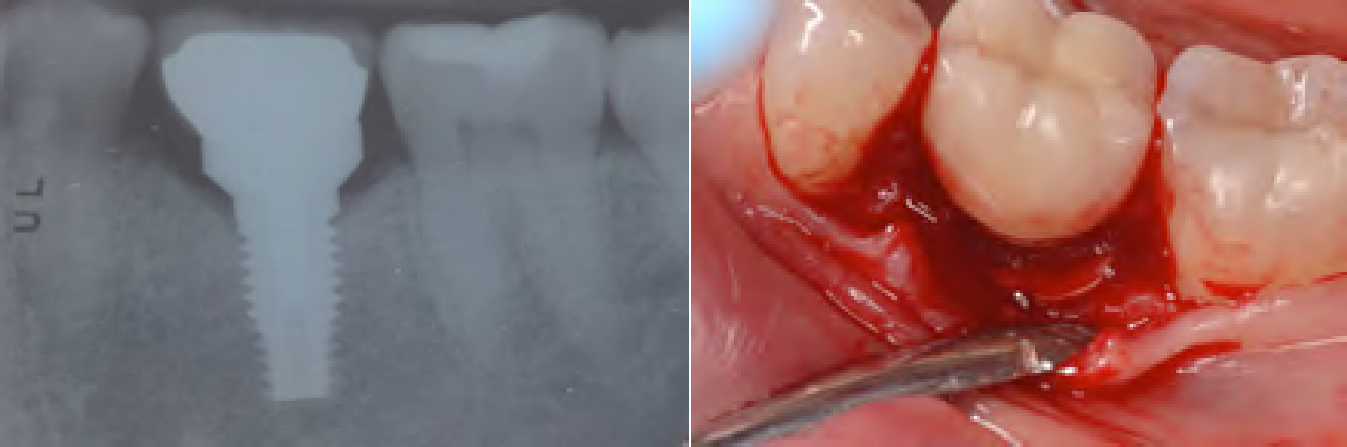

Fig 7. Radiograph showing a poorly fitting restoration that contributes to peri-implant disease, because open/tight marginal ridge contacts allow food impaction, while occlusal trauma can develop due to failure to recognize the different dynamics between teeth and implants.

Figure 7

Fig 10. Radiographs (left) are not reliable methods for evaluating cement excess. The deeper the position of the margin, the greater the amount of undetected cement that can be discovered with flaps (right).

Figure 10